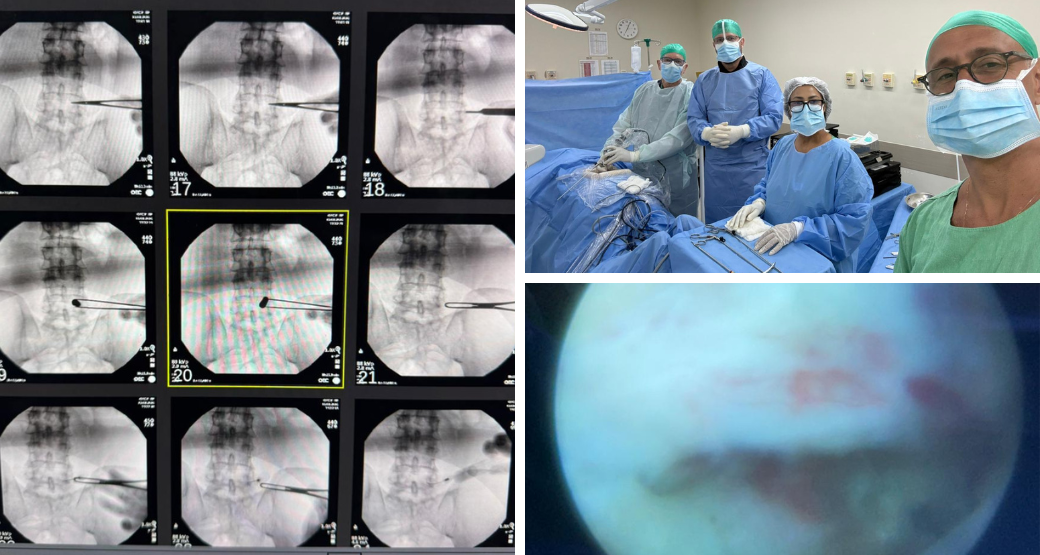

Cirurgia endoscópica em 03.02

Durante o procedimento, após a retirada do ligamento amarelo, os doutores Edward Robert e Renato Bastos identificaram de forma nítida a compressão da raiz L5.

“Posteriormente, essa compressão ocorria pelo ligamento amarelo e pelo processo articular e, anteriormente, por alterações degenerativas da face posterior do corpo vertebral de L5”, ressaltam.

Um achado particularmente relevante

Segundo os cirurgiões, foi a visualização, por meio do vídeo endoscópico, que detectou sinais evidentes de hiperemia na raiz descendente de L5, após a liberação do componente compressivo, indicando sofrimento radicular prévio.

“Após a completa descompressão da raiz espinhal, associada à limpeza cuidadosa do processo articular e da região posterior do canal vertebral, finalizamos o procedimento com sucesso”, comemora a equipe cirúrgica.

Participaram da cirurgia endoscópica: Edward Robert Orr e Renato Bastos (cirurgiões ortopédicos), Bruno Rangel (anestesiologista), além da instrumentadora cirúrgica Marisa Brandão.